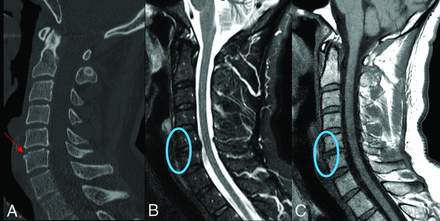

Fracture-negative, radiologist false positive, CNN false positive case example. Sagittal (A) cervical spine CT image and sagittal (B) STIR and sagittal (C) T1-weighted cervical spine MR images demonstrate a small depression along the anterosuperior margin of the C6 vertebral body (red arrow) without associated bone marrow edema, prevertebral edema, or disc space widening (blue circles). This case example illustrates how both the radiologist and CNN algorithm are capable of ignoring the absence of secondary signs, such as prevertebral edema and disc space widening when incorrectly identifying a fracture.